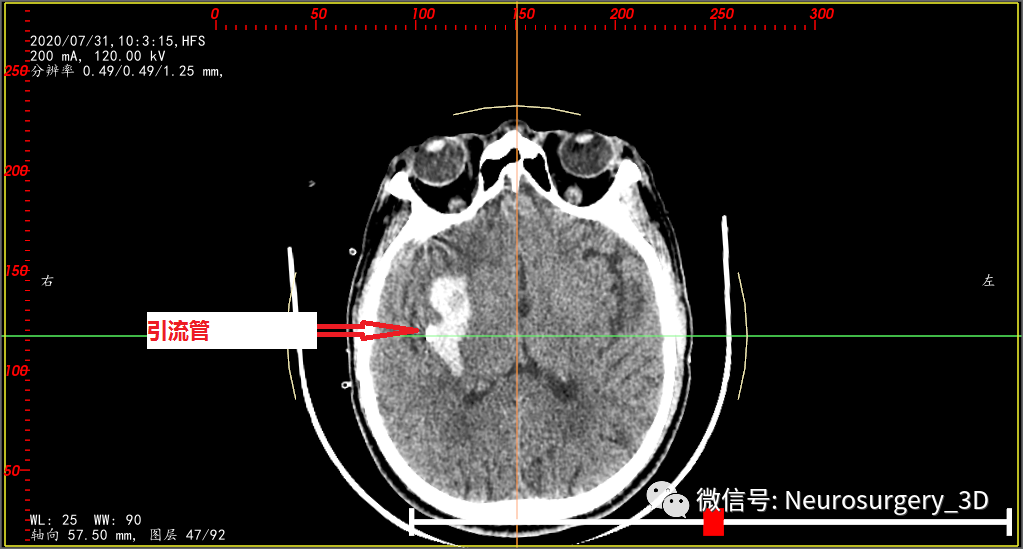

随着液态血肿增加而意识加重的症状在液态血肿引流后明显好转,术后第一天CT(2020年7月31日)复查:

术后第一天血肿重建,残余血肿17ml

还原术后引流管(绿色)与术前血肿、穿刺路径关系

融合术前血肿(红色)与术后血肿(蓝色)、术后引流管(绿色),可术后计算不同时间的血肿清除率。

术后第一天复查CT后应用尿激酶一次,2020年8月2日CT复查后给予拔除引流管。